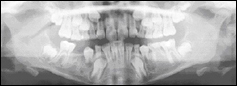

| Handwurzelaufnahme zur Bestimmung der individuellen Reife des Patienten | Fernröntgenseitenbild (FRS) zur Beurteilung der Kieferbeziehung aus seitlicher Sicht |